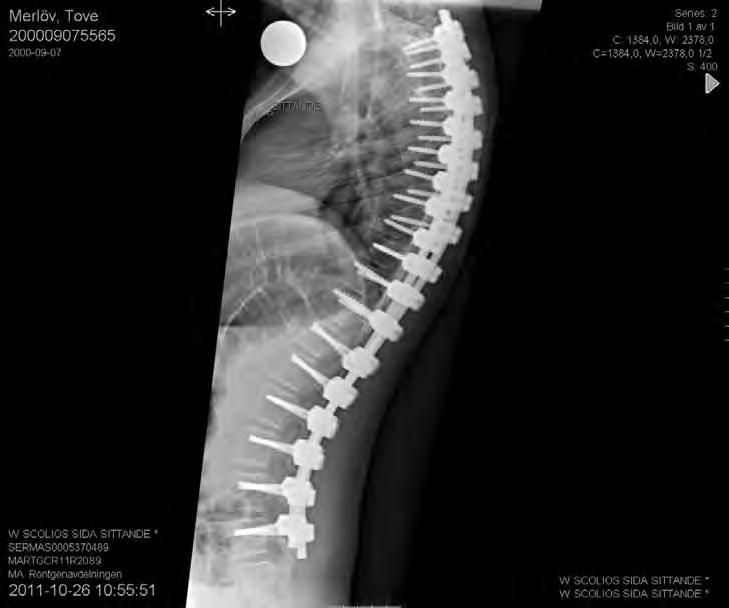

Operativ behandling

Vid operation för neuromuskulär skolios har man i allmänhet större blodförlust än vid idio-

11-årig flicka med CP och spastisk tetrapares. Hon hade en extremt snabb skoliosutveckling från Cobb 45 grader till drygt 70 grader på tre månader. detta föranledde en snar op från Th2 till L5 med transpedikulära skruvar enl. Suk. Blödningen uppgick till 1500 ml. Postoperativt har vi inga restriktioner avseende mobiliseringen då så många fixationspunkter användes. Patienten hade postoperativt lunginflammation som dock snabbt svarade på antibiotikabehandling.

patisk skolios varför preoperativ tappning för autolog transfusion bör övervägas. Korrektion och fusion är ofta indicerade då

Cobbvinkeln är 40 – 60 grader. Vid CP är en bakre operationsmetod idag den vanligaste. Traditionellt har man använt sublaminär stag-

fixation med cerclage, en utveckling som Luque i Mexico utvecklade i slutet av 1970-talet. Idag används allt oftare transpedikulära skruvar enligt Suk från Sydkorea. Ett ständigt debattämne är när man ska inkludera bäckenet i instrumenteringen. Ett snedställt bäcken över 20 grader brukar ofta anges som indikation för denna åtgärd. Bäckenet och dess ställning kan betraktas som en del av deformiteten som helhet och är linjen rak från L4 och ner till bäckenet kan man enligt egen erfarenhet ofta stanna vid L5 och förlita sig på den ofta utomordentligt väl utvecklade iliolumbala ligamentapparaten. Vid operationen brukar instrumenteringen sträcka sig från övre bröstryggen (Th 1 – Th 2) till L5 eller bäckenet. I de mest krökta delarna av ryggen gör man ofta multipla bakre lösningar. Det går till så att man gör fenestreringar intill epiduralrummet och resecerar intervertebrallederna. Vanligtvis sätter vi skruvar i samtliga tillgängliga pediklar för att fördela lasterna under själva korrektionen så man inte riskerar en tidig skruvlossning (pull out). I rigida fall använder vi oss av reduktionsskruvar som har en förlängning av skruvarnas gängor, man fördelar då krafterna till många skruvar under korrektionsfasen. När korrektionen är färdig biter man av skruvhuvudsförlängningarna. Stagtjockleken ska vara så stor som patientens konstitution tillåter, framförallt för att få en bättre korrektion men också för att minska risken för stagbrott. Ibland använder vi ett grövre stag på korrektionssidan, den konkava och djupare belägna sidan och ett med mindre diameter på den konvexa sidan där implantaten ligger mer ytligt.

12 årig flicka med CP. Hon hade fått en starkt försämrad sittställning på grund av progressiv lumbal skolios. vid opererationen användes bakre teknik för att först få korrektion av den lumbala skoliosen. Operationen extenderades ovan Th12 med tunnare stag som är längre än nödvändigt vid operationstillfället. Syftet var att man med denna konstruktion (Shilla-teknik) har stag som ska kunna glida i skruvhuvudena i bröstryggen, allt för att kunna få thorax att växa ytterligare. I thorakalryggen infördes skruvarna transmuskulärt med hjälp av navigationsutrustning för att inte stimulera till bakre fusion.

Lateral bild av övre delen av konstruktionen där de ”för långa” stagen syns väl.

Blodförlust under ingreppet var c:a 500 ml.